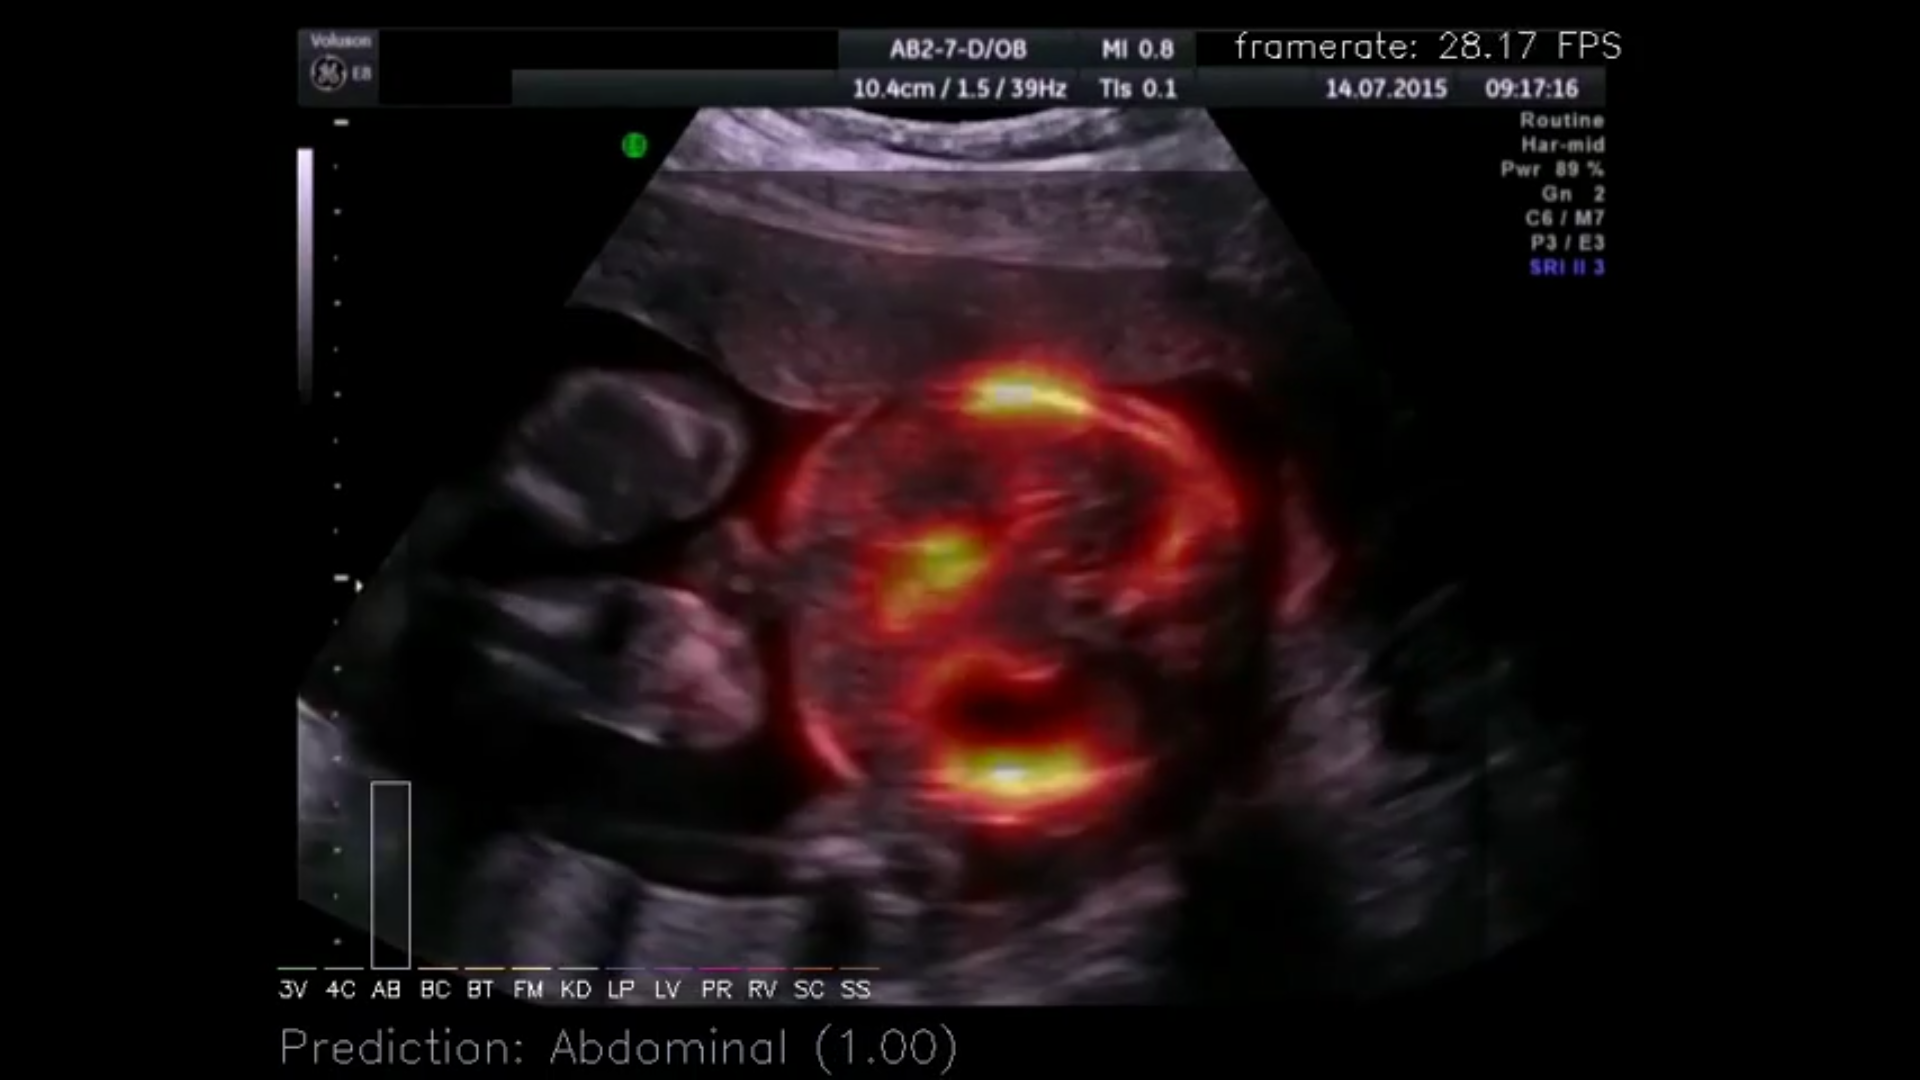

Our research is broad and does not always fit neatly into predefined categories. Nonetheless, a substantial part of our work can be understood as contributing to improved uncertainty quantification and interpretability in machine learning, as well as to the development of methods that generalize across tasks.

Interpretable Machine Learning

Meta-Learning and Generalization Across Tasks

Robustness, Safety and Uncertainty

In medical image analysis, confidently predicting something false can have devastating consequences. Apart from achieving high predictive accuracy, one needs to establish…